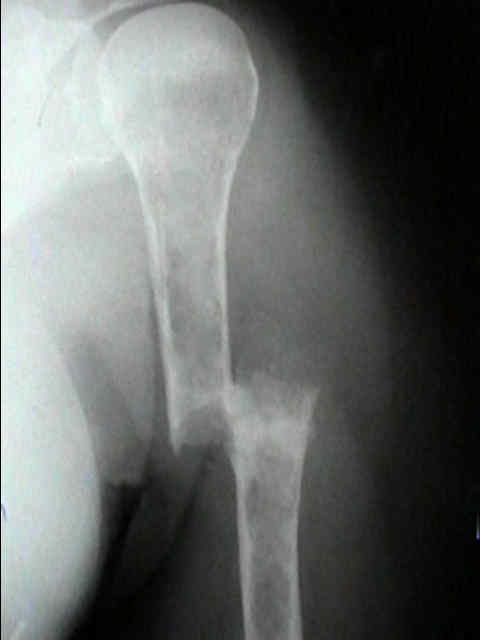

Radiographic Studies

- standard x-rays may show diffuse osteopenia

- "punched-out lesions" w/ no surrounding new-bone formation;

- over time lesions may change from diffuse osteopenia to more permeative moth-eaten destructive pattern, sometimes w/ cortical expansion;

- bone destruction occurs w/ little or no reactive bone formation unless pathologic frx is present;

- myeloma may present as solitary lesion or more commonly a diffuse tumor, involving multiple bones, including vertebrae, skull, pelvis and femurs;